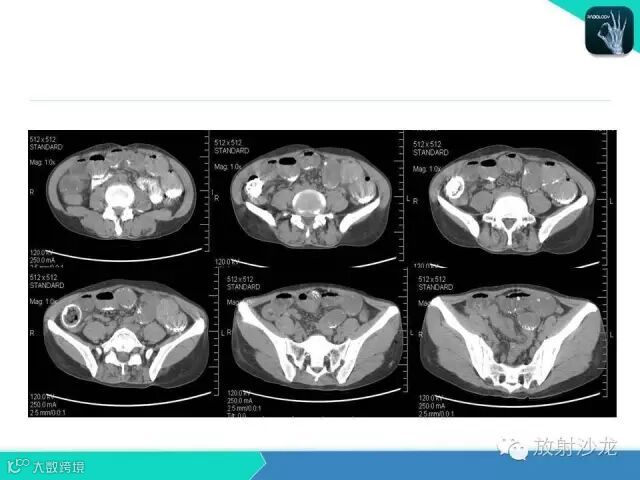

肠梗阻的分类及影像诊断